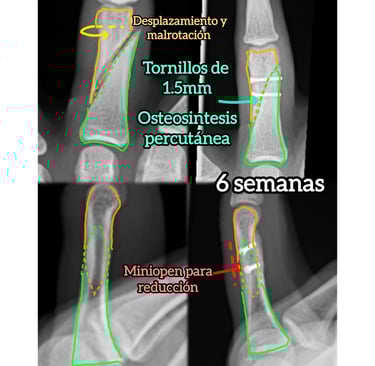

Radiografías para confirmar el tipo de fractura y su desplazamiento

En casos complejos puede ser necesario ampliar el estudio para planificar correctamente el tratamiento.

Existe deformidad o rotación del dedo

Desplazamiento significativo

Inestabilidad

Afectación articular

Deformidad o rotación del dedo

La cirugía busca restaurar la anatomía, permitiendo una movilización más precoz y una mejor recuperación funcional.